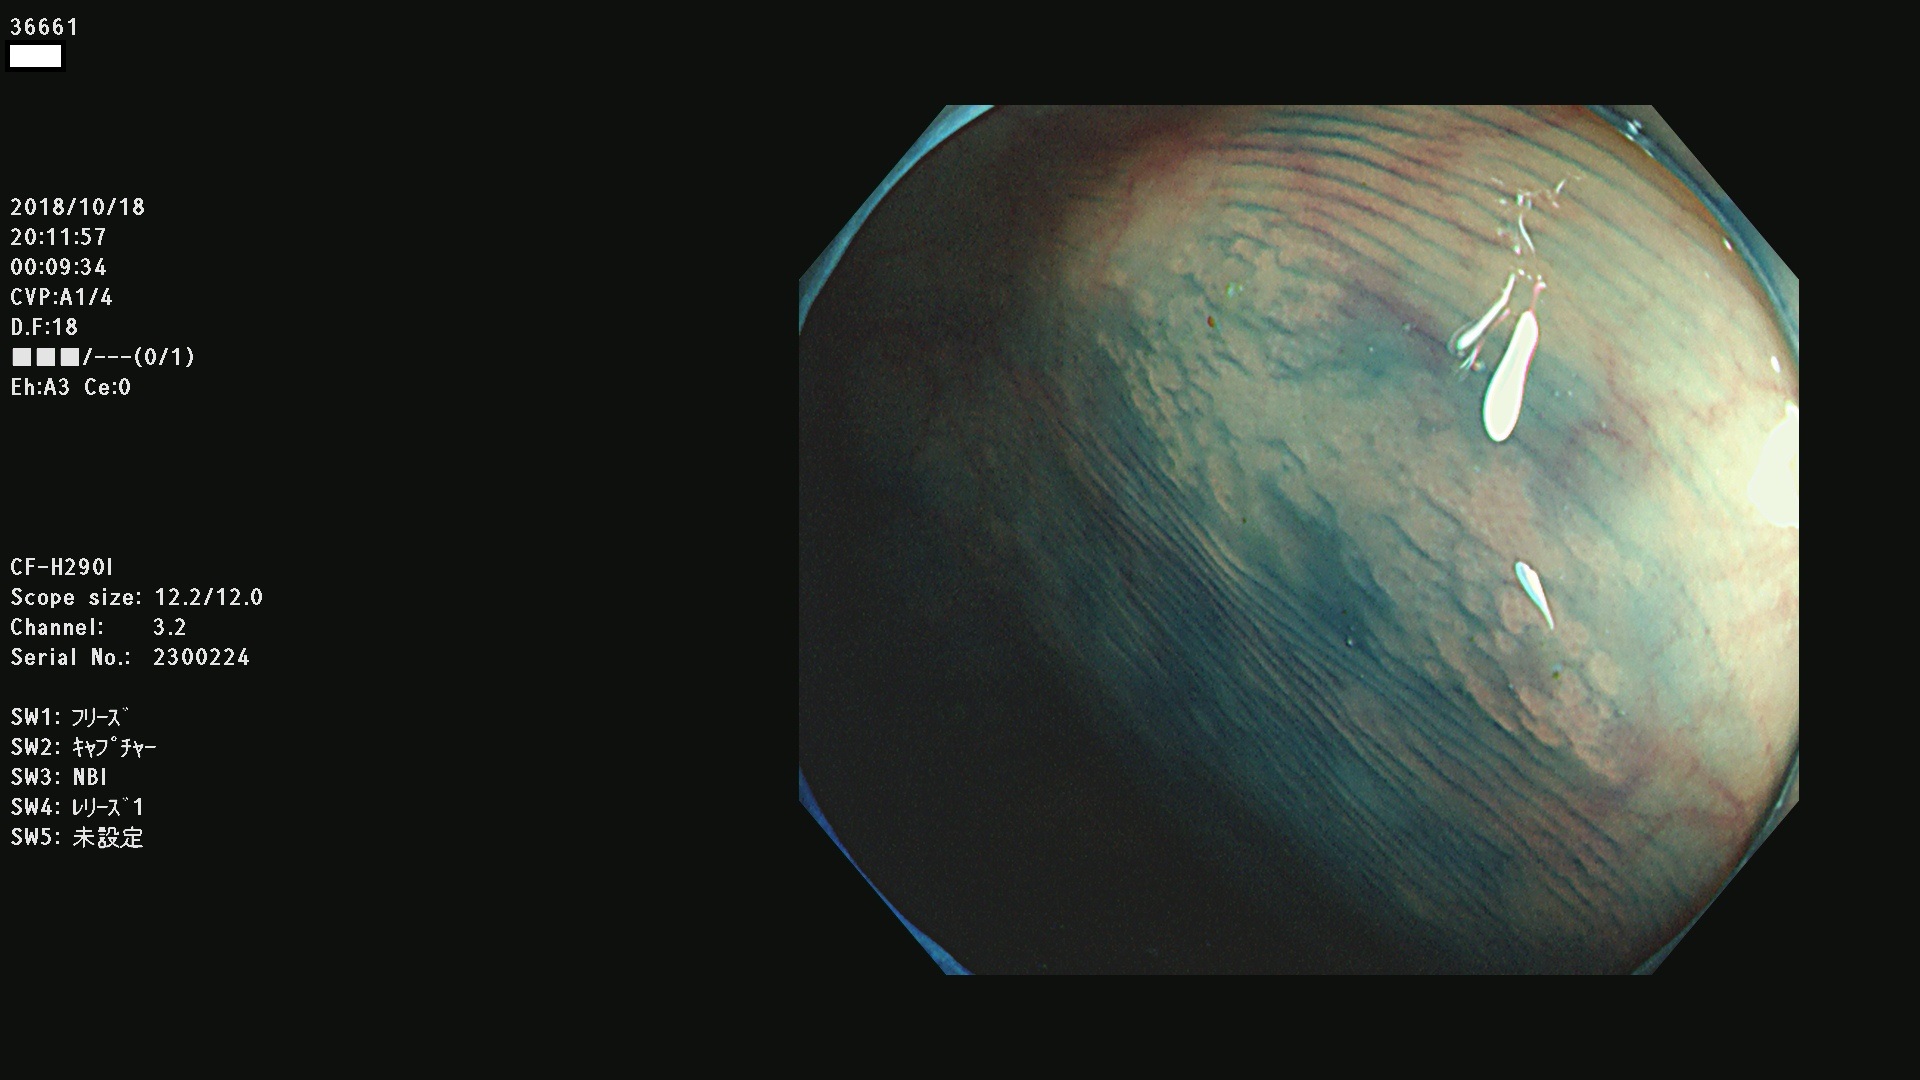

36600 36601 36603 36605 36606 36608 36609 36610 36611 36612 36613 36615 36617 36620 36621 36624 36625 36626 36627 36628 36629 36631(SSAPのみ) 36632 36633 36634 36636(SSAPのみ) 36637(SSAPのみ) 36639 36640 36642 36643 36644 36646 36647 36648 36649(SSAPのみ) 36650(SSAPのみ) 36652 36653 36654 36655(SSAPのみ) 36656 36657 36658 36659 36660 36661(SSAPのみ) 36665 36668 36669 36672 36673 36676 36677 36678 36679 36681 36682 36683 36684 36685 36687(SSAPのみ) 36691 36692 36693 36694 36695 36696 36697 36699(SSAPのみ)

発見困難で危険性の高い平坦型病変(上記100名より抽出)